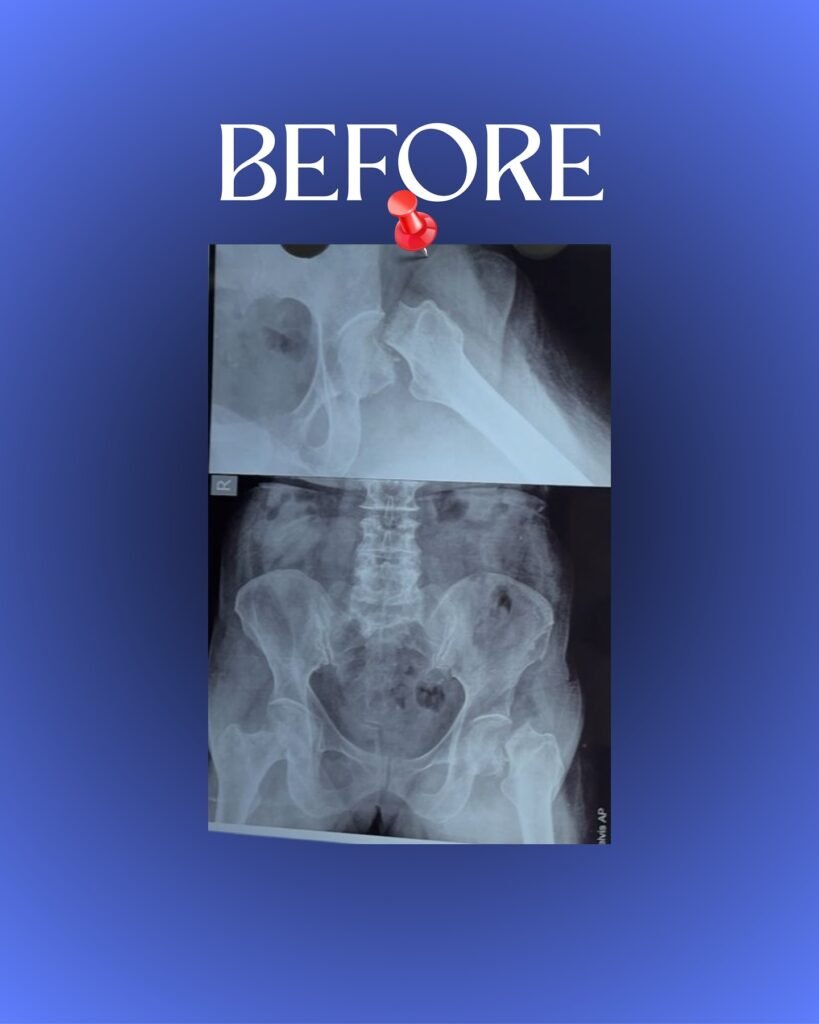

Before performing a hip replacement in Jabalpur, Dr. Nachiket Pansey carries out a detailed evaluation, including X-rays, MRI scans, and medical tests. This helps identify the extent of joint damage and allows him to design a personalized surgical plan. His careful approach ensures every patient receives the most suitable hip implant and achieves the best results from their hip arthroplasty.